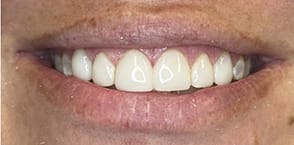

A 46-year-old female patient presented with the chief complaint of disliking the shape, color, and spacing of her front teeth. After conducting online research, the patient was adamant she did not want veneers or traditional bonding but instead preferred Bioclear® composite restorations (Bioclear, bioclearmatrix.com) on her maxillary and mandibular anterior teeth to preserve tooth structure. An intraoral scan using the iTero Element® 2 intraoral scanner (Align Technology, Inc, itero.com) and photographs were taken. It was discussed with the patient that prior to final restorations Invisalign® clear aligner therapy (Align Technology, Inc, invisalign.com) was needed to close all mandibular spacing (eliminating the need for restorations) and partially close the maxillary spacing (improving the height-to-width ratios of the final maxillary restorations). The patient completed Invisalign treatment in 15 weeks and then whitened with Opalescence™ PF 10% whitening gel (Ultradent, ultradent.com). An intraoral scan with the iTero Element 2 scanner was taken for a pre-prosthetic lab wax-up of teeth Nos. 6 through 11. These teeth were restored with full esthetic composite veneers using the Bioclear heated composite injection overmolding technique with Filtek™ Supreme Ultra Universal Restorative White Body paste and flowable (3M Oral Care, 3m.com). No tooth structure was resected. The patient was immediately scanned for Vivera® retainers. She was thrilled with her smile transformation.

Direct composite restorations with the Bioclear method

are minimally invasive, additive, and esthetically natural looking.